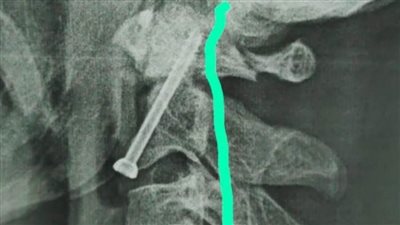

مستشفى سوهاج الجامعي تجري جراحة دقيقة بالعمود الفقري لشاب بعد سقوطه من أعلى نخلة